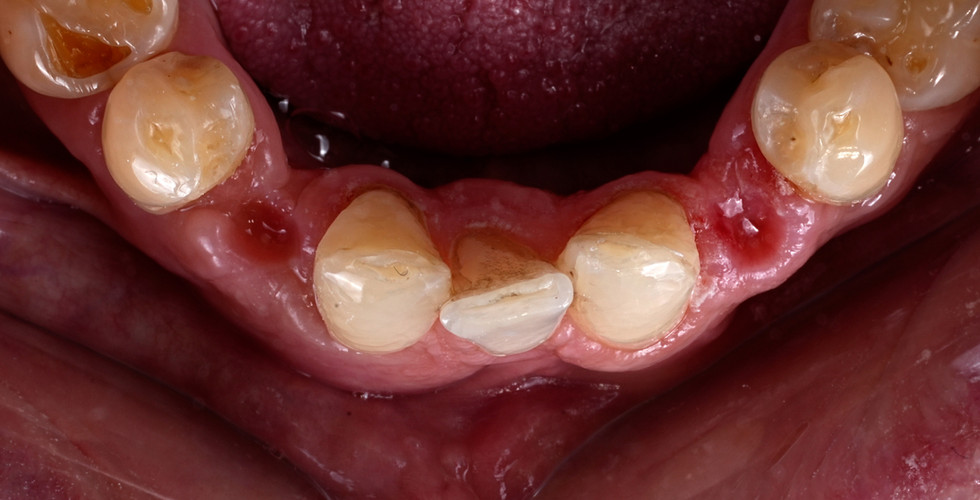

Fallbeispiel - Zahnhalsdeckung

Freiliegende Zahnhälse können nicht nur Schmerzen verursachen, sondern auch das Risiko für Karies und Entzündungen erhöhen. Kalte Getränke, süße Speisen oder schon die Zahnbürste werden plötzlich zur Qual.

Mit Zahnhalsdeckungen decken wir Bereiche ab, die sich schneller durch umwelteinflüsse abnutzen (Erosion, Attrition, falsche Putztechnik), reduzieren die Empfindlichkeit und stellen die natürliche Harmonie Ihres Lächelns wieder her.